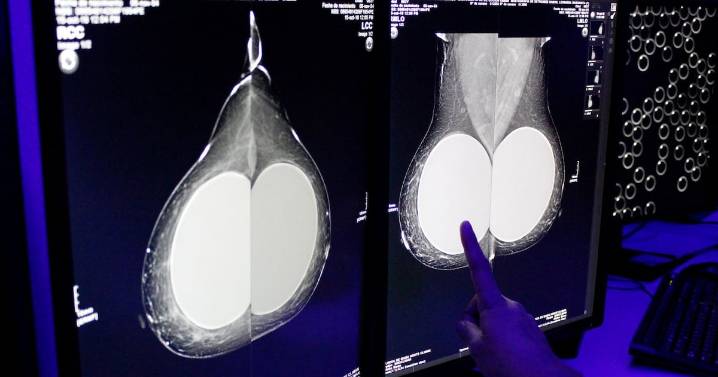

El Laboratorio Nacional de Inteligencia Artificial (LNIA) en México representa un paso significativo hacia la soberanía digital y la innovación tecnológica en el país. Además de representar beneficios para el sector salud .